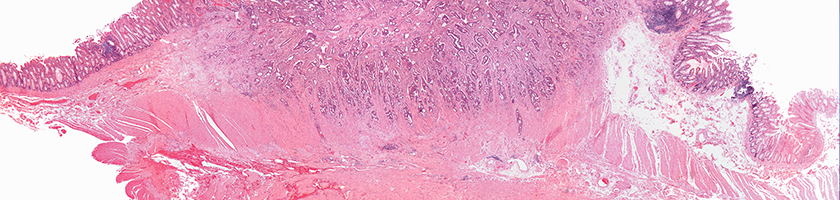

GI cancers form when malignant cells grow in certain tissues of the GI system.

Colorectal cancers form when malignant cells grow in the colon or the rectum.

Types of Colorectal and GI Cancer

Colorectal and GI cancers include cancer of the stomach, colon, rectum, small intestine, gallbladder, bowels, and anus.